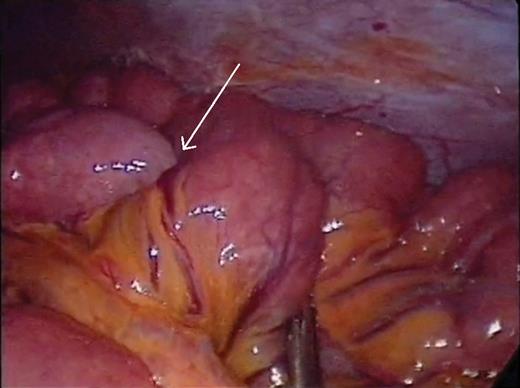

Small bowel intussusception (arrow) that did not reduce spontaneously.

A 41-year-old female presented with 3 weeks of intermittent crampy epigastric abdominal pain, nausea and diarrhea. She was able to tolerate a liquid diet but not solids. She had one episode of vomiting and lost 6 lbs over the course of 3 weeks. Her vital signs, physical examination and laboratory studies were unremarkable. She did not have a history of prior abdominal surgery or malignancy. A CT scan demonstrated two areas of small bowel intussusception (Fig. 1A and B), without evidence of bowel obstruction or mass. The patient underwent exploratory laparoscopy using a 5 mm 30° camera and two 5 mm working ports. Six separate regions of intussusception within the small bowel were discovered between 55 and 130 cm from the ligament of Treitz. All areas of intussusception were short and witnessed to undergo spontaneously reduction (Fig. 2A and B), except for one (Fig. 3), which was resected through a mini-laparotomy. There was no obvious evidence of masses, adhesions or serosal abnormalities along the small bowel. There were prominent lymph nodes noted in the small bowel mesentery (Fig. 4). The postoperative course was uneventful and she was discharged 4 days after her operation. She had resolution of symptoms and had no recurrence after 3 years of follow-up. Pathologic examination of the small bowel demonstrated no evidence of malignancy, lead point, pathologic changes or sprue. Likewise, there was no evidence of acid-fast organisms, fungal or helminth parts identified. The enlarged mesenteric lymph nodes demonstrated reactive follicular hyperplasia and multifocal non-necrotizing lipogranulomas.